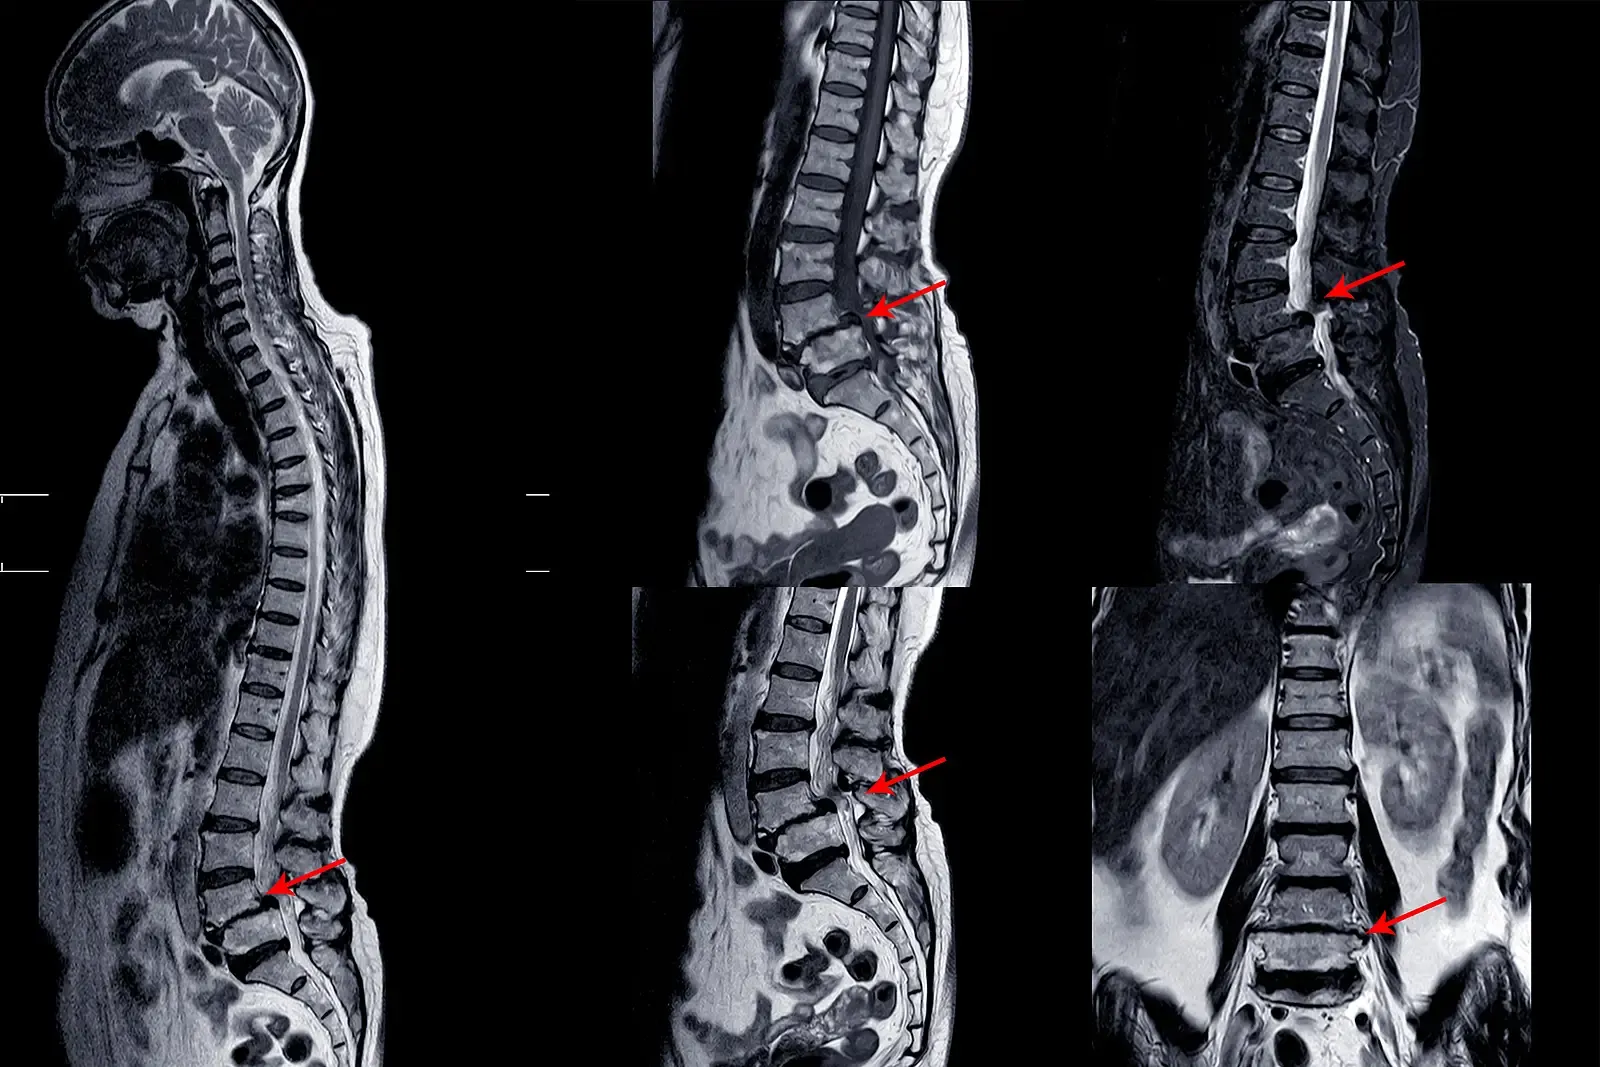

After 30 Days I had a final appointment with Dr. Chen

Dr. Chen couldn't believe the functional improvement scores:

"Michael's pain-free activity duration increased by 340% in just 30 days.

His fear-avoidance scores dropped from severe to moderate."

"Most importantly, he'd gone from needing assistance with 7 daily tasks to needing assistance with zero."

"Your movement patterns don't match what we saw six months ago," Dr. Chen told Michael

"I've never seen improvement like this in such a short time period."